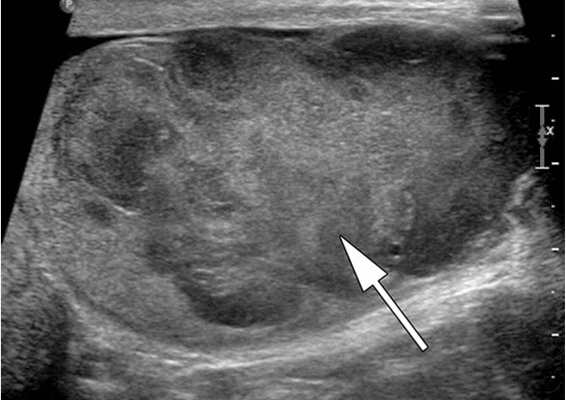

Ультразвуковое исследование (УЗИ) мошонки является предпочтительным начальным визуализирующим исследованием для оценки образования яичка. УЗИ может подтвердить наличие новообразования, определить его расположение и оценить состояние противоположного яичка (рис. 4). Чувствительность метода достаточно высокая - от 92 % до 98 %.

Компьютерная томография органов грудной клетки, брюшной полости, малого таза используются для оценки распространения опухолевого процесса (рис.5).

![Снимок УЗИ яичка]()

Снимок УЗИ яичка